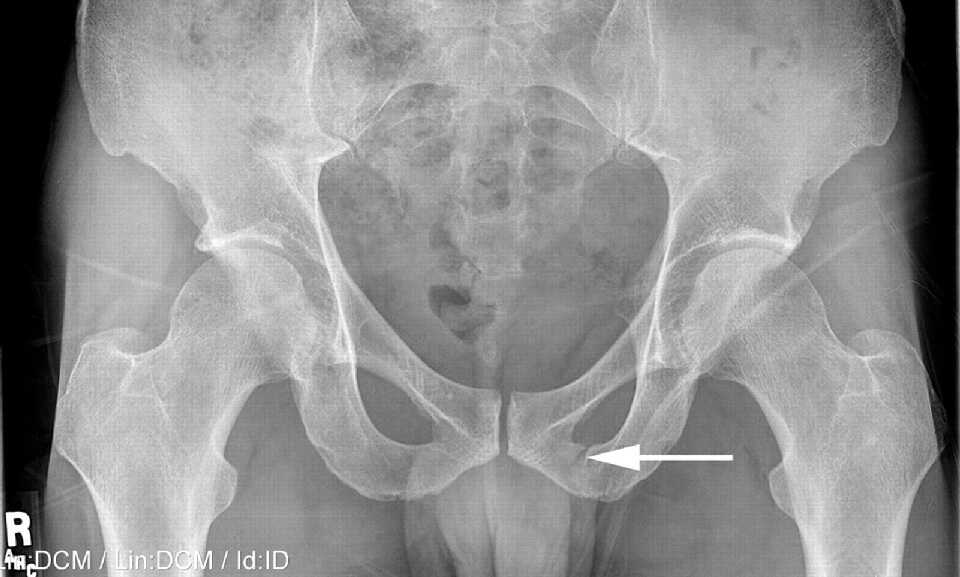

Рентгеновские снимки крестцово-копчикового отдела позвоночника